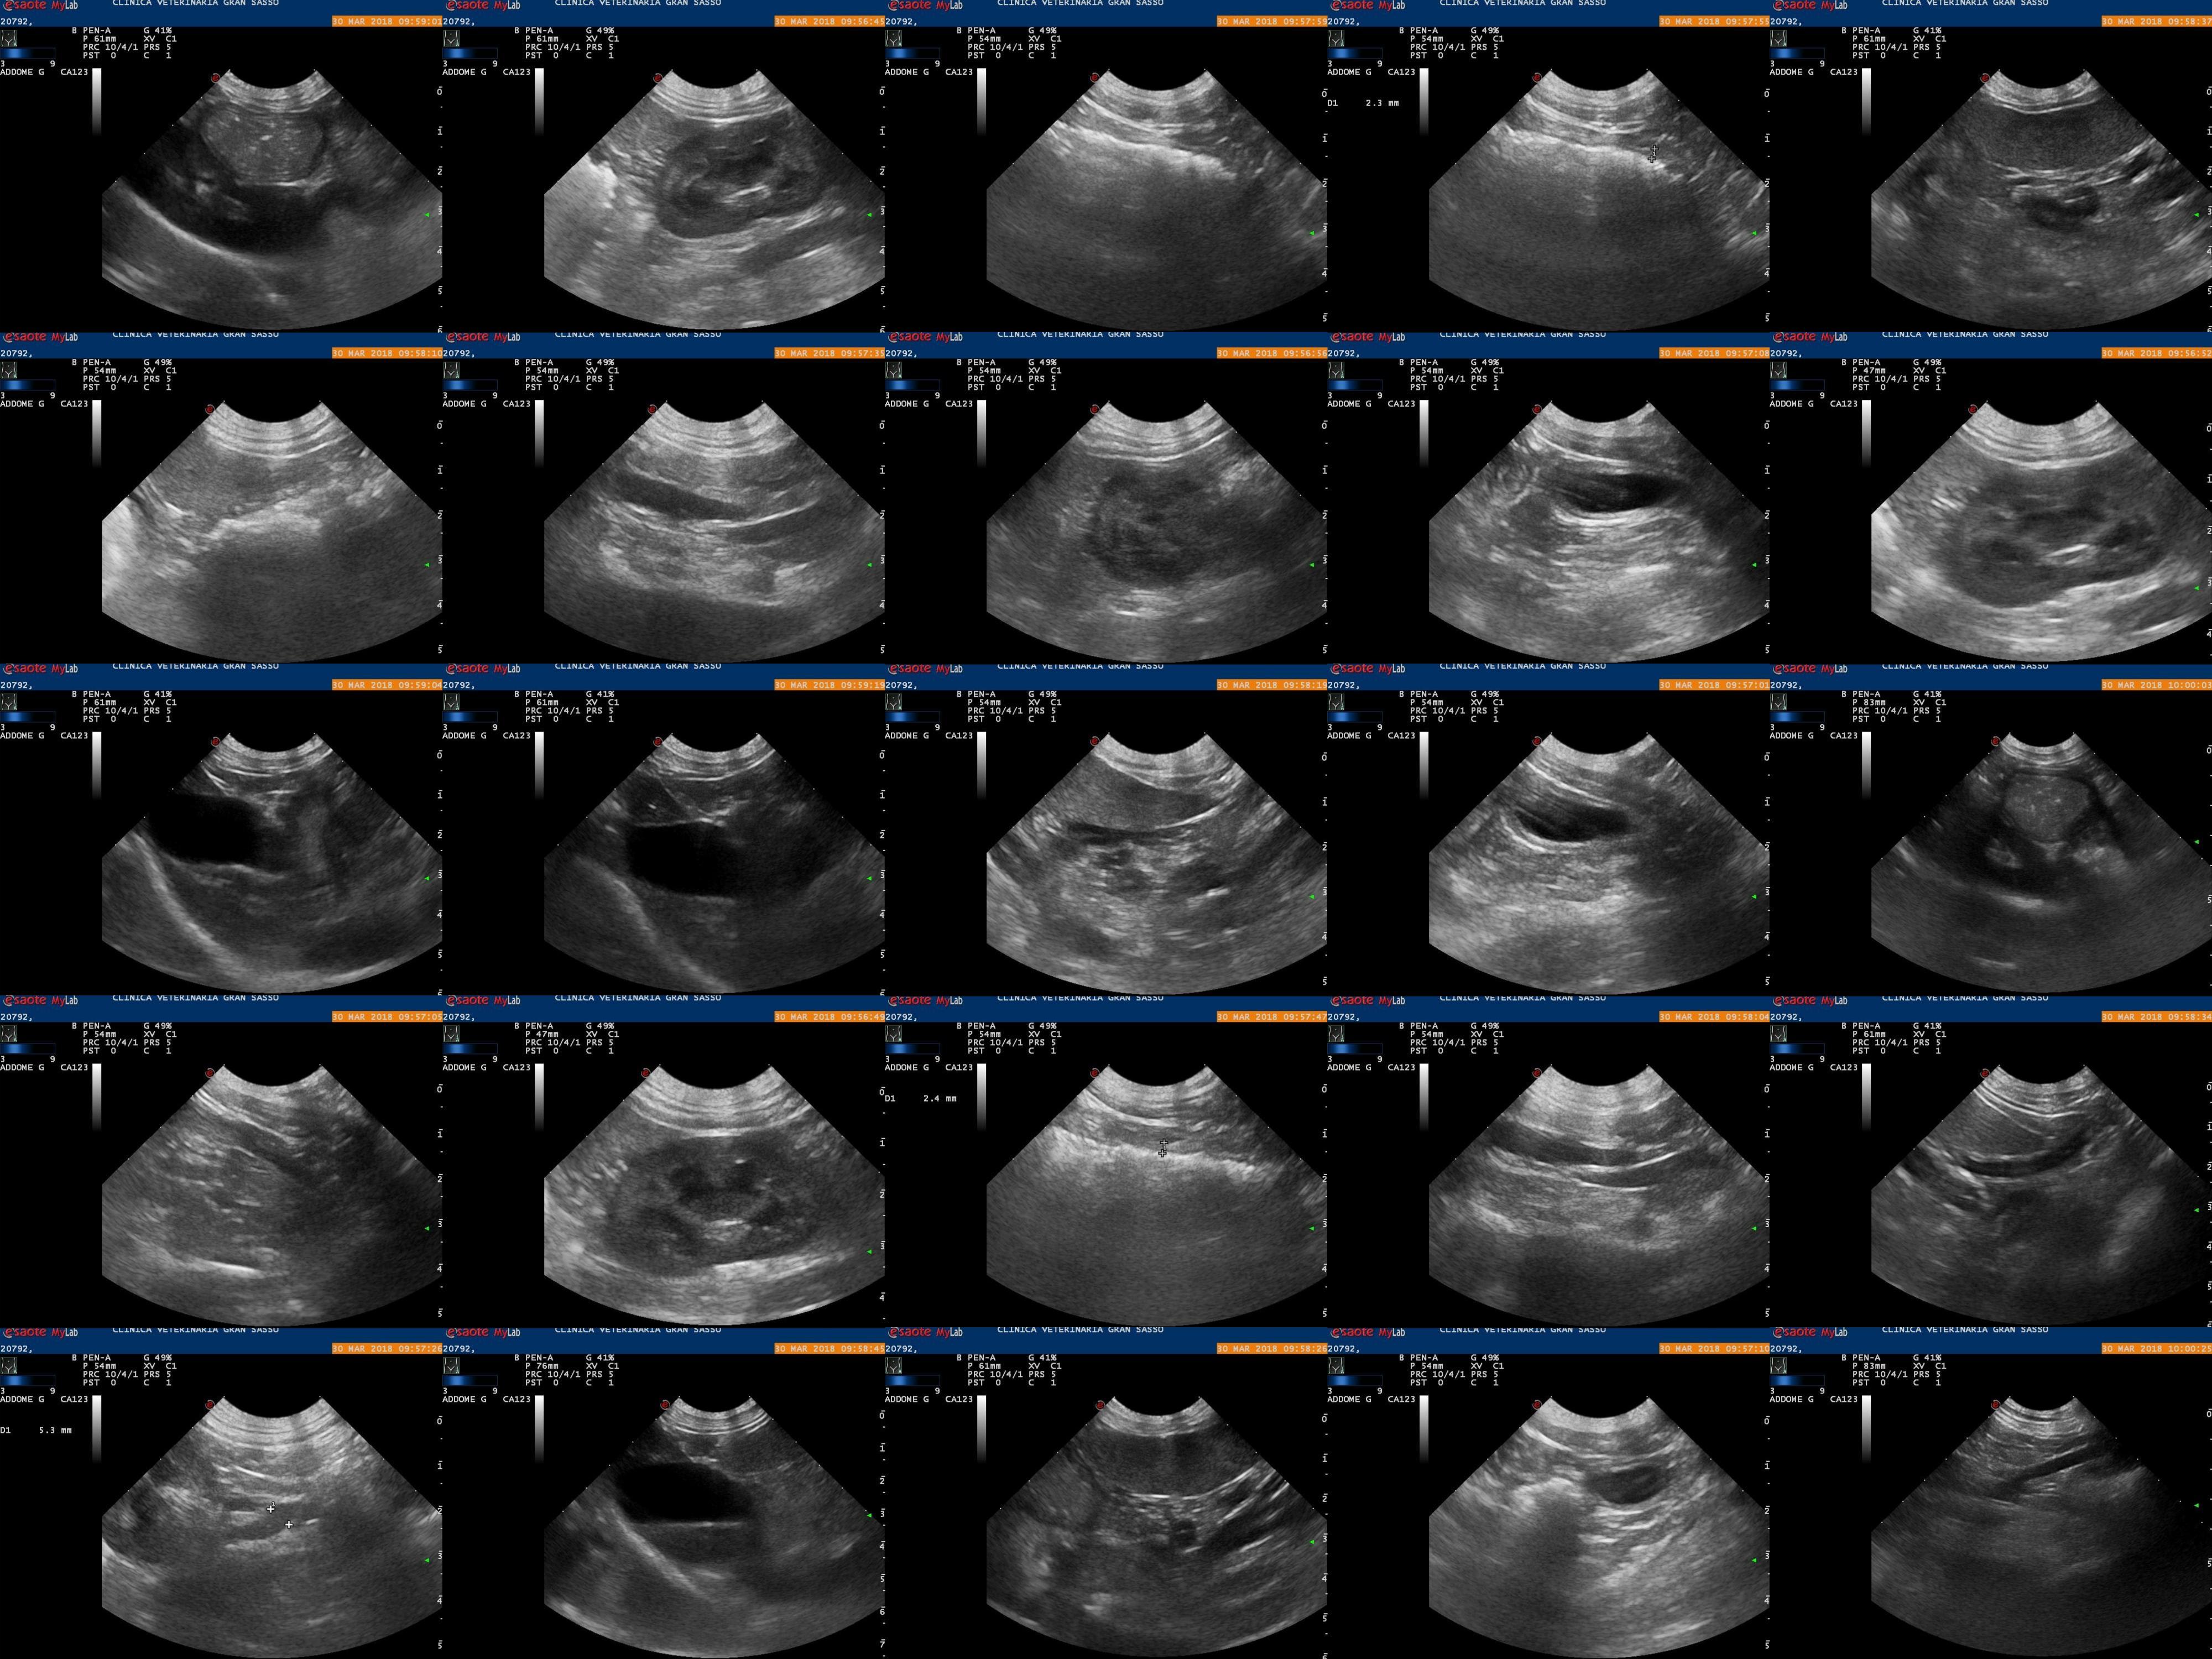

Beatrice display hypomotility, pain, temporary shaking after walking, lip licking and yellow feces. Doctors are unsure if it is enteritis, pancreatitis, or disk herniation. Thank you in advance for your help, Luca

Those are all possible causes. In cases like this, we usually need to treat symptomatically. The normal treatments for pancreatitis would also treat enteritis. Beatrice would need an MRI to determine if she has a herniated disk, but she could be treated with pain medication (which she also needs for possible pancreatitis) in the mean time. I can't tell you which issue is the cause (or they are all a factor) from these images, but I share your vet's concern about all of them.